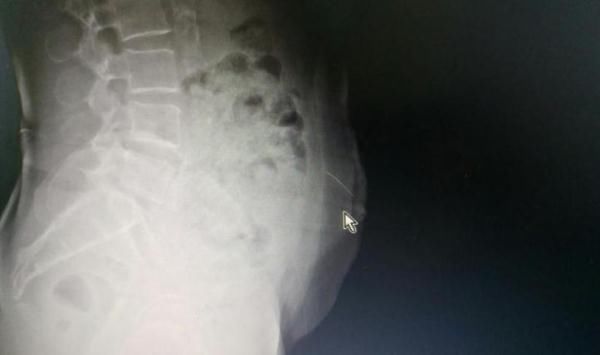

影像显示阿婆断针的位置

入院后,了解到阿婆的行为,医生第一时间通过拍片发现,针还在梁阿婆腹壁里。由于针灸用针又细又长,稍有不慎可能扎到腹腔内脏器,带来严重危害。

广医三院肝胆外科副主任医师潘裕国说,“由于腹壁是运动的,患者弯腰、转身等动作都可能导致锋利的针深入游走,插到内脏导致肠穿孔,甚至扎到腹壁下动脉导致血管大出血。同时,在家自行针灸,所用的针未必经过了严格消毒程序,若不及时取出有可能导致深部软组织感染和破伤风。”因此,留在体内的针此刻就像一枚定时炸弹,随时会给患者带来生命危险。